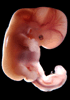

Carnegie Stage 18 (44 post-ovulatory days)

Most embryos at stage 18 are approximately 44 postovulatory days old and measure 13-17 mm in length. Distinguishing criteria for this stage include cervical and lumbar flexures, distinct notching in the hand plate, the first appearance of the elbow, eyelid folds may appear in more advanced specimens, and auricular hillocks begin to form distinct parts of the external ear.

Photographs